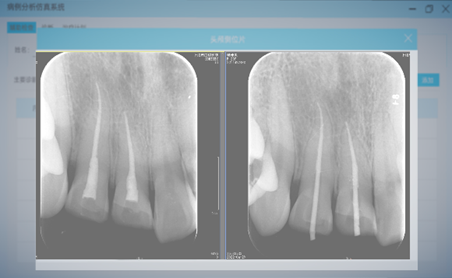

l 根尖片判读(图7):点击“影像学检查结果”按钮,进入根尖片判读界面。学生可对虚拟患者的根尖片进行观察,提交自己的解读报告。在考核模式下,系统根据预设定点标准位置给与客观化评分,在训练模式下,提供定点提示功能,辅助初学者训练。

图7. 根尖片判读界面